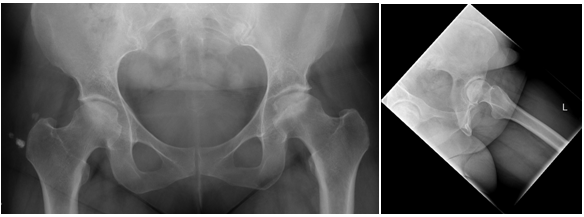

Patient was thereafter counseled and prepared for surgery. 3.2mm guide pin was inserted through the lateral cortex into the centre of the osteonecrotic portion of the femoral head. DHS core reamer was placed over the guide pin and this was drilled to within 5 mm of subchondral bone. Bone graft was inserted into the defect just lateral to the sclerotic bone defect visualized on fluoroscopy. Then we inserted a 9 x 25 mm bio absorbable interference screw into the neck containing the bone graft (Figure 2).

Figure 2 Preoperative MRI with left hip avascular necrosis .There is mild edema in the left femoral head and neck. No subchondral bone depression identified.